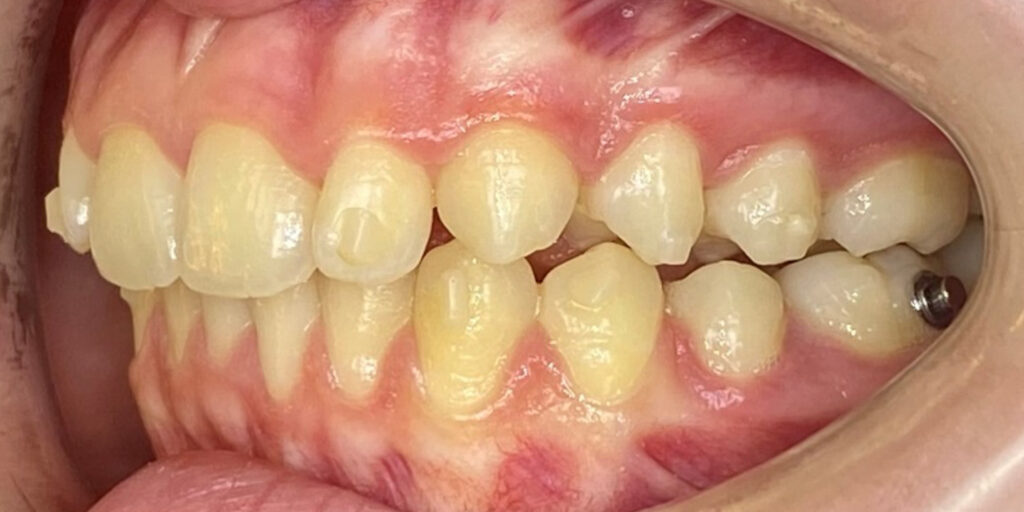

After undergoing maxillary expansion, Dr. Sorina Blaj assessed the patient again in September 2021, and at that point, tooth 84 had exfoliated, tooth 44 had erupted, and tooth 23 had started to erupt.

After considering that 23 no longer needed to be surgically exposed, Dr. Blaj, the patient, and her parents decided to use Spark Clear Aligners to correct dental issues. The treatment began in November 2021, utilizing the 3D Approver Software™ to design a digital plan. The plan aims to:

The treatment includes sequential distalization of the maxillary teeth and mesialization of 3.6, virtual extraction of 74, composite attachments on all distalizing teeth, class II elastics, bite ramps on upper central incisors, IPR and eruption guides for teeth 23 and 35.

The Spark eruption guides are used to guide and save space for semi-erupted teeth that will naturally be brought down into occlusion or using auxiliary techniques. The software marks them with the letter “E” for easy identification.